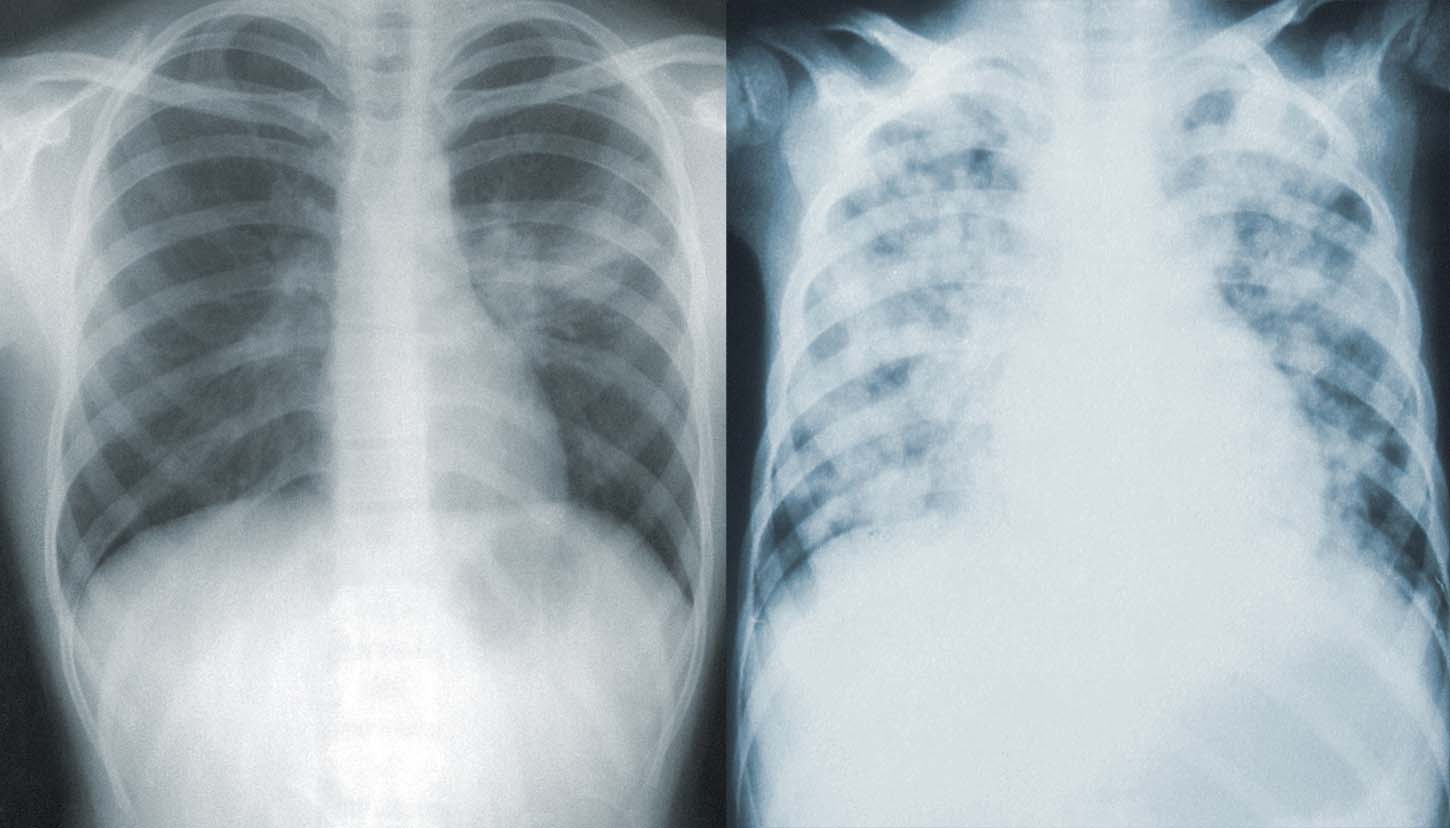

- 숨쉬기가 힘들어졌다 (질식할 것 같다).

- 가슴에 통증이 생겼다, 혹은, 가슴이 짖눌리는 것 같다.

- 정신이 혼미해졌다.

- 입술이나 얼굴이 푸른색이 되었다.